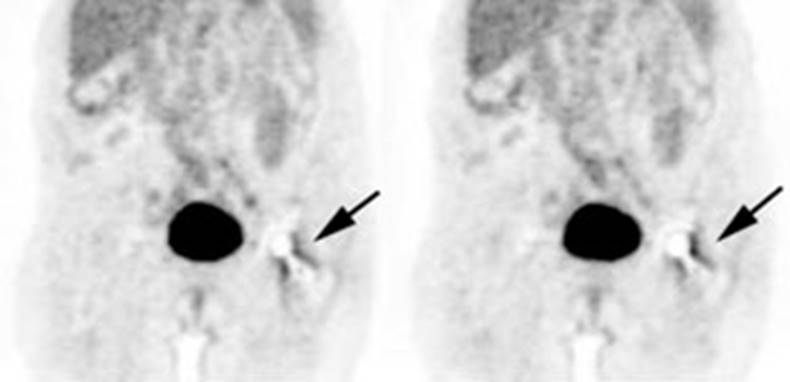

Figure 24 - Normal

uterine activity: Faint

uterine uptake is common (black arrows).